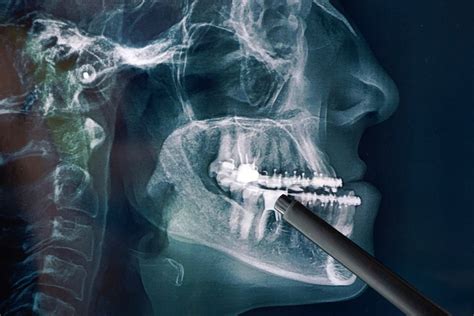

Radiología Maxilofacial y Oral

Los radiólogos orales y maxilofaciales son los que se encarga de realizar e interpretar las imágenes orales y de los elementos adyacentes. A través de estas se identifican diferentes enfermedades y afecciones en la boca y la estructura maxilofacial. Cuando se habla de imágenes orales y maxilofaciales se incluyen, las radiografías, resonancias magnéticas, imágenes intraorales, ultrasonidos y otras. Las radiografías ayudan a cualquier especialista, ya que a través de estas es posible ver el desarrollo de los dientes, encontrar caries, observar las raíces de los dientes y la estructura ósea.